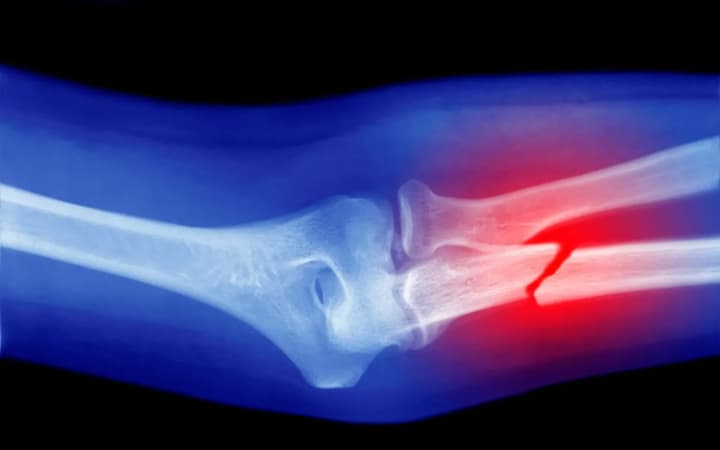

Ці фактори призводять до руйнівних процесів, що ослаблюють кісткову структуру та підвищують ризик переломів.

Особливе занепокоєння викликали дослідження на тваринах: накопичення мікропластику знижувало кількість лейкоцитів і погіршувало мікроструктуру кісток, що загрожує їхньою крихкістю та деформаціями.